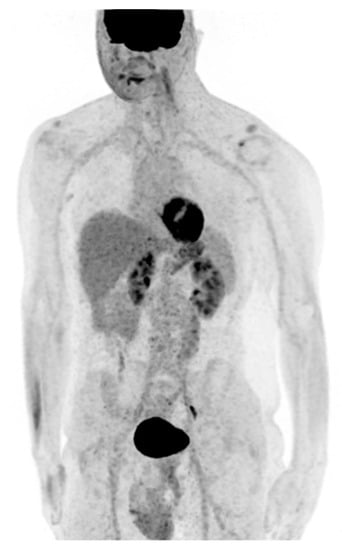

2.1. Pre-Surgical Intervention Imaging